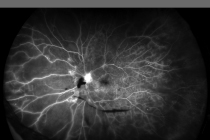

- フルオレセイン蛍光眼底造影(FAG)

増殖性糖尿病網膜症(FA)